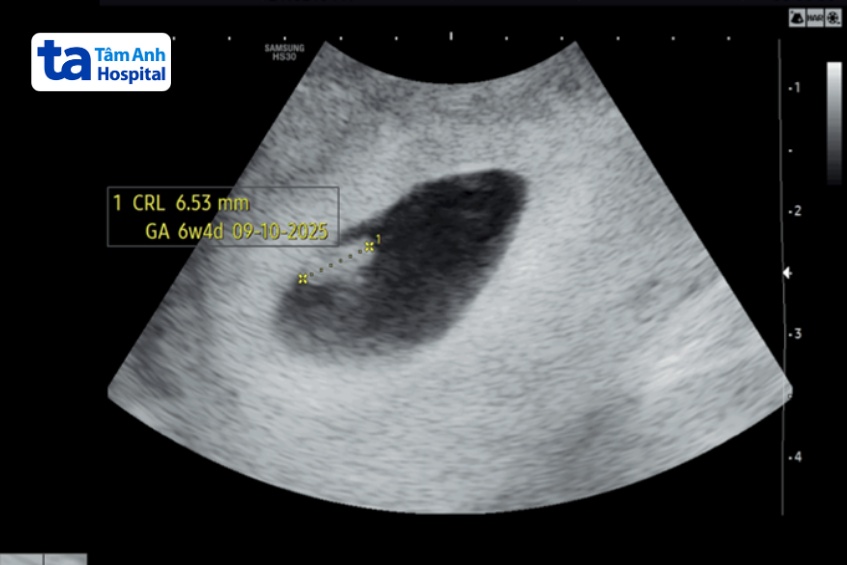

Sau khi được tư vấn, vợ chồng chị Hằng quyết định thực hiện thụ tinh ống nghiệm (IVF). Bác sĩ chỉ định sử dụng thuốc kích trứng vừa phải để đạt số trứng lý tưởng, tránh nguy cơ quá kích buồng trứng. Sau một lần chọc hút trứng, chị Hằng tạo được 3 phôi ngày 5 loại tốt và 2 phôi ngày 6 loại khá. Chị được chuyển một phôi loại tốt nhất vào tử cung, số còn lại trữ đông. Chị Hằng đậu thai ngay lần đầu, thai kỳ hiện hơn 6 tuần.